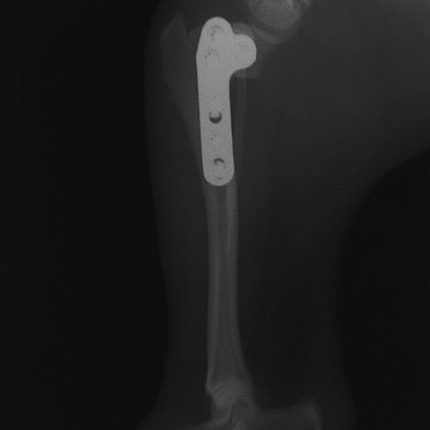

バーニーズマウンテンドック 4歳 避妊♀

突然の右後肢跛行を主訴に来院されました。整形外科学的検査において右膝に脛骨圧迫テストで陽性、前方引き出し徴候が認められました。神経学的検査において特に異常は認められませんでした。レントゲン検査において、関節液の貯留所見や脛骨の前方変位の所見が認められました。

関節鏡検査を実施いたしました。関節鏡検査では、重度の滑膜炎および前十字靭帯の完全断裂が認められました。半月板に損傷は認められませんでした。

断裂前十字靭帯の除去を行いました。その後 TTA(Tibial tuberosity advancement)を実施しました。

術後経過は良好で、後肢機能・筋肉量の改善目的で現在はリハビリテーションを行っています。